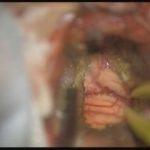

術中写真

摘出 前